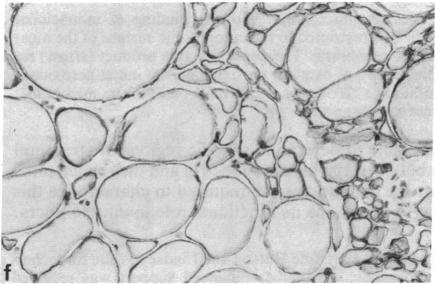

Spectrin is the major protein of the erythrocyte membrane skeleton, which is bound to the cytoplasmic surface of the membrane's lipid bilayer and is responsible for cell shape and membrane elasticity. Inability to identify spectrin in other cell types led to the assumption that this protein was unique to erythrocytes. However, spectrin-like proteins have been demonstrated recently in a variety of cell types, including skeletal and cardiac muscle, in several species. We used monoclonal antibodies against human erythrocyte spectrin subunits in an immunocytochemical study to detect related proteins in normal and diseased human skeletal muscle. Six of seven monoclonal antibodies against beta-spectrin determinants were bound at the cytoplasmic surface of muscle fiber plasma membranes, whereas none of six monoclonal antibodies against alpha-spectrin determinants was bound. Muscle fibers of patients with neuromuscular diseases showed similar distribution and specificity of antibody binding to those of normal subjects, but the intensity of binding was increased. In contrast, probable regenerating fibers in muscle of patients with muscular dystrophies showed reduced binding of antibodies, but reduced binding was not seen in fetal muscle fibers nor in those of a patient with a myotubular myopathy. We conclude that human skeletal muscle fibers possess a spectrin-related protein associated with their plasma membrane that shows extensive beta-chain similarities to erythrocyte spectrin but differs significantly with respect to the alpha-subunit. Its function may be associated with the maintenance of membrane and myofibril integrity during contraction, and the increased antibody binding in diseased muscle may reflect a structural rearrangement of spectrin or a compensatory increase in spectrin abundance in response to increased stress on these systems.

血影蛋白是红细胞膜骨架的主要蛋白质,它与膜脂双层的细胞质表面结合,负责细胞形状和膜弹性。在其他细胞类型中未能鉴定出血影蛋白,导致人们认为这种蛋白质是红细胞特有的。然而,最近在包括骨骼肌和心肌在内的多种细胞类型中,在几个物种中都发现了血影蛋白样蛋白。我们在一项免疫细胞化学研究中使用针对人红细胞血影蛋白亚基的单克隆抗体,来检测正常和患病的人骨骼肌中的相关蛋白。针对β-血影蛋白决定簇的七种单克隆抗体中有六种与肌纤维质膜的细胞质表面结合,而针对α-血影蛋白决定簇的六种单克隆抗体均未结合。神经肌肉疾病患者的肌纤维显示出与正常受试者相似的抗体结合分布和特异性,但结合强度增加。相比之下,肌营养不良症患者肌肉中可能正在再生的纤维显示出抗体结合减少,但在胎儿肌纤维或患有肌管性肌病的患者的肌纤维中未观察到结合减少。我们得出结论,人骨骼肌纤维拥有一种与其质膜相关的血影蛋白相关蛋白,该蛋白与红细胞血影蛋白在β链上有广泛的相似性,但在α亚基方面有显著差异。其功能可能与收缩过程中膜和肌原纤维完整性的维持有关,患病肌肉中抗体结合增加可能反映了血影蛋白的结构重排或血影蛋白丰度的代偿性增加,以应对这些系统上增加的压力。